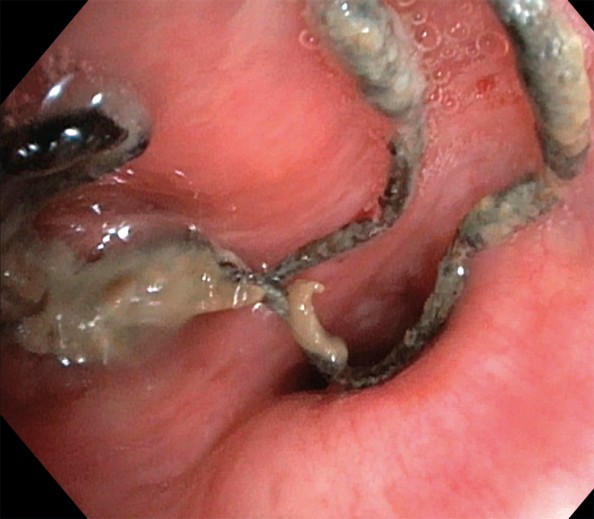

På bildet, tatt ved bronkoskopi, ses suturmateriale og purulent slim som ligger endobronkialt, nær ostiet for det apikale underlappssegment på høyre side.

Pasienten er en kvinne i 50-årene. Som barn ble hun operert med partiell høyresidig underlappsektomi. Man lot det apikale underlappssegmentet stå igjen, og det ble brukt ikke-resorberbar tråd. Etter operasjonen har hun hatt tilbakevendende nedre luftveisinfeksjoner, alt fra bronkitt til pneumoni. Forut for den aktuelle bronkoskopien ble det gjort CT thorax som avdekket abscessutvikling (CT-bilde). Ved utredning fant man ingen underliggende immunsvikt eller andre forklaringer på infeksjonstendensen. Hun røyker daglig, men har ingen obstruktiv lungesykdom. Suturmaterialet som ble avdekket ved bronkoskopi var i retrospekt synlig på CT thorax-bildet, men kunne muligens mistolkes som sekret i luftveiene.

Suturmateriale er som et fremmedlegeme og fremmer dannelse av en biofilm og bakteriekolonisering. Dette er høyst sannsynlig årsaken til gjentatte pneumonier og utviklingen av lungeabscess (1). De synlige suturene lot seg fjerne med tang bronkoskopisk. Prosedyren ble gjort først etter at pasienten hadde gjennomført langvarig antibiotikabehandling. Selv om det hadde gått mer enn 40 år siden operasjonen fant sted, var ikke suturmaterialet brutt ned. I litteraturen har vi funnet bare få rapporter om fjerning av aspirert fremmedlegeme med tilsvarende tidsspenn fra aspirasjon til fjerning (2). I disse tilfellene har indikasjonen for utredningen vært tilbakevendende pneumonier, slik som hos vår pasient. Det vi kan lære av kasuistikken, er at hos pasienter med gjentatte nedre luftveisinfeksjoner av ukjent årsak bør man vurdere CT thorax og bronkoskopi.